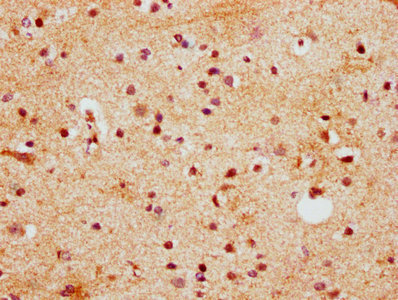

IHC image of CSB-PA010685LA01HU diluted at 1:400 and staining in paraffin-embedded human brain tissue performed on a Leica BondTM system. After dewaxing and hydration, antigen retrieval was mediated by high pressure in a citrate buffer (pH 6.0). Section was blocked with 10% normal goat serum 30min at RT. Then primary antibody (1% BSA) was incubated at 4°C overnight. The primary is detected by a biotinylated secondary antibody and visualized using an HRP conjugated SP system.